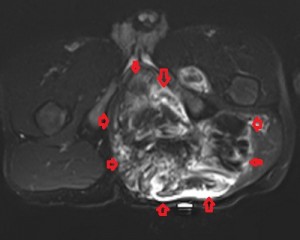

All the images in the lower panel are MR images (from left to right, axial unenhanced T1; fat-suppressed T1 post-gadolinium; coronal T1 without fat suppression; fat-suppressed sagittal T2). They show the extent of the disease better than CT and confirm that it is primarily lipomatous with little soft-tissue content. It infiltrates most of the left gluteal muscles, occupies the entire left perineum and ischiorectal fossa, and extends proximally in the retroperitoneum to the level of the sacral promontory.